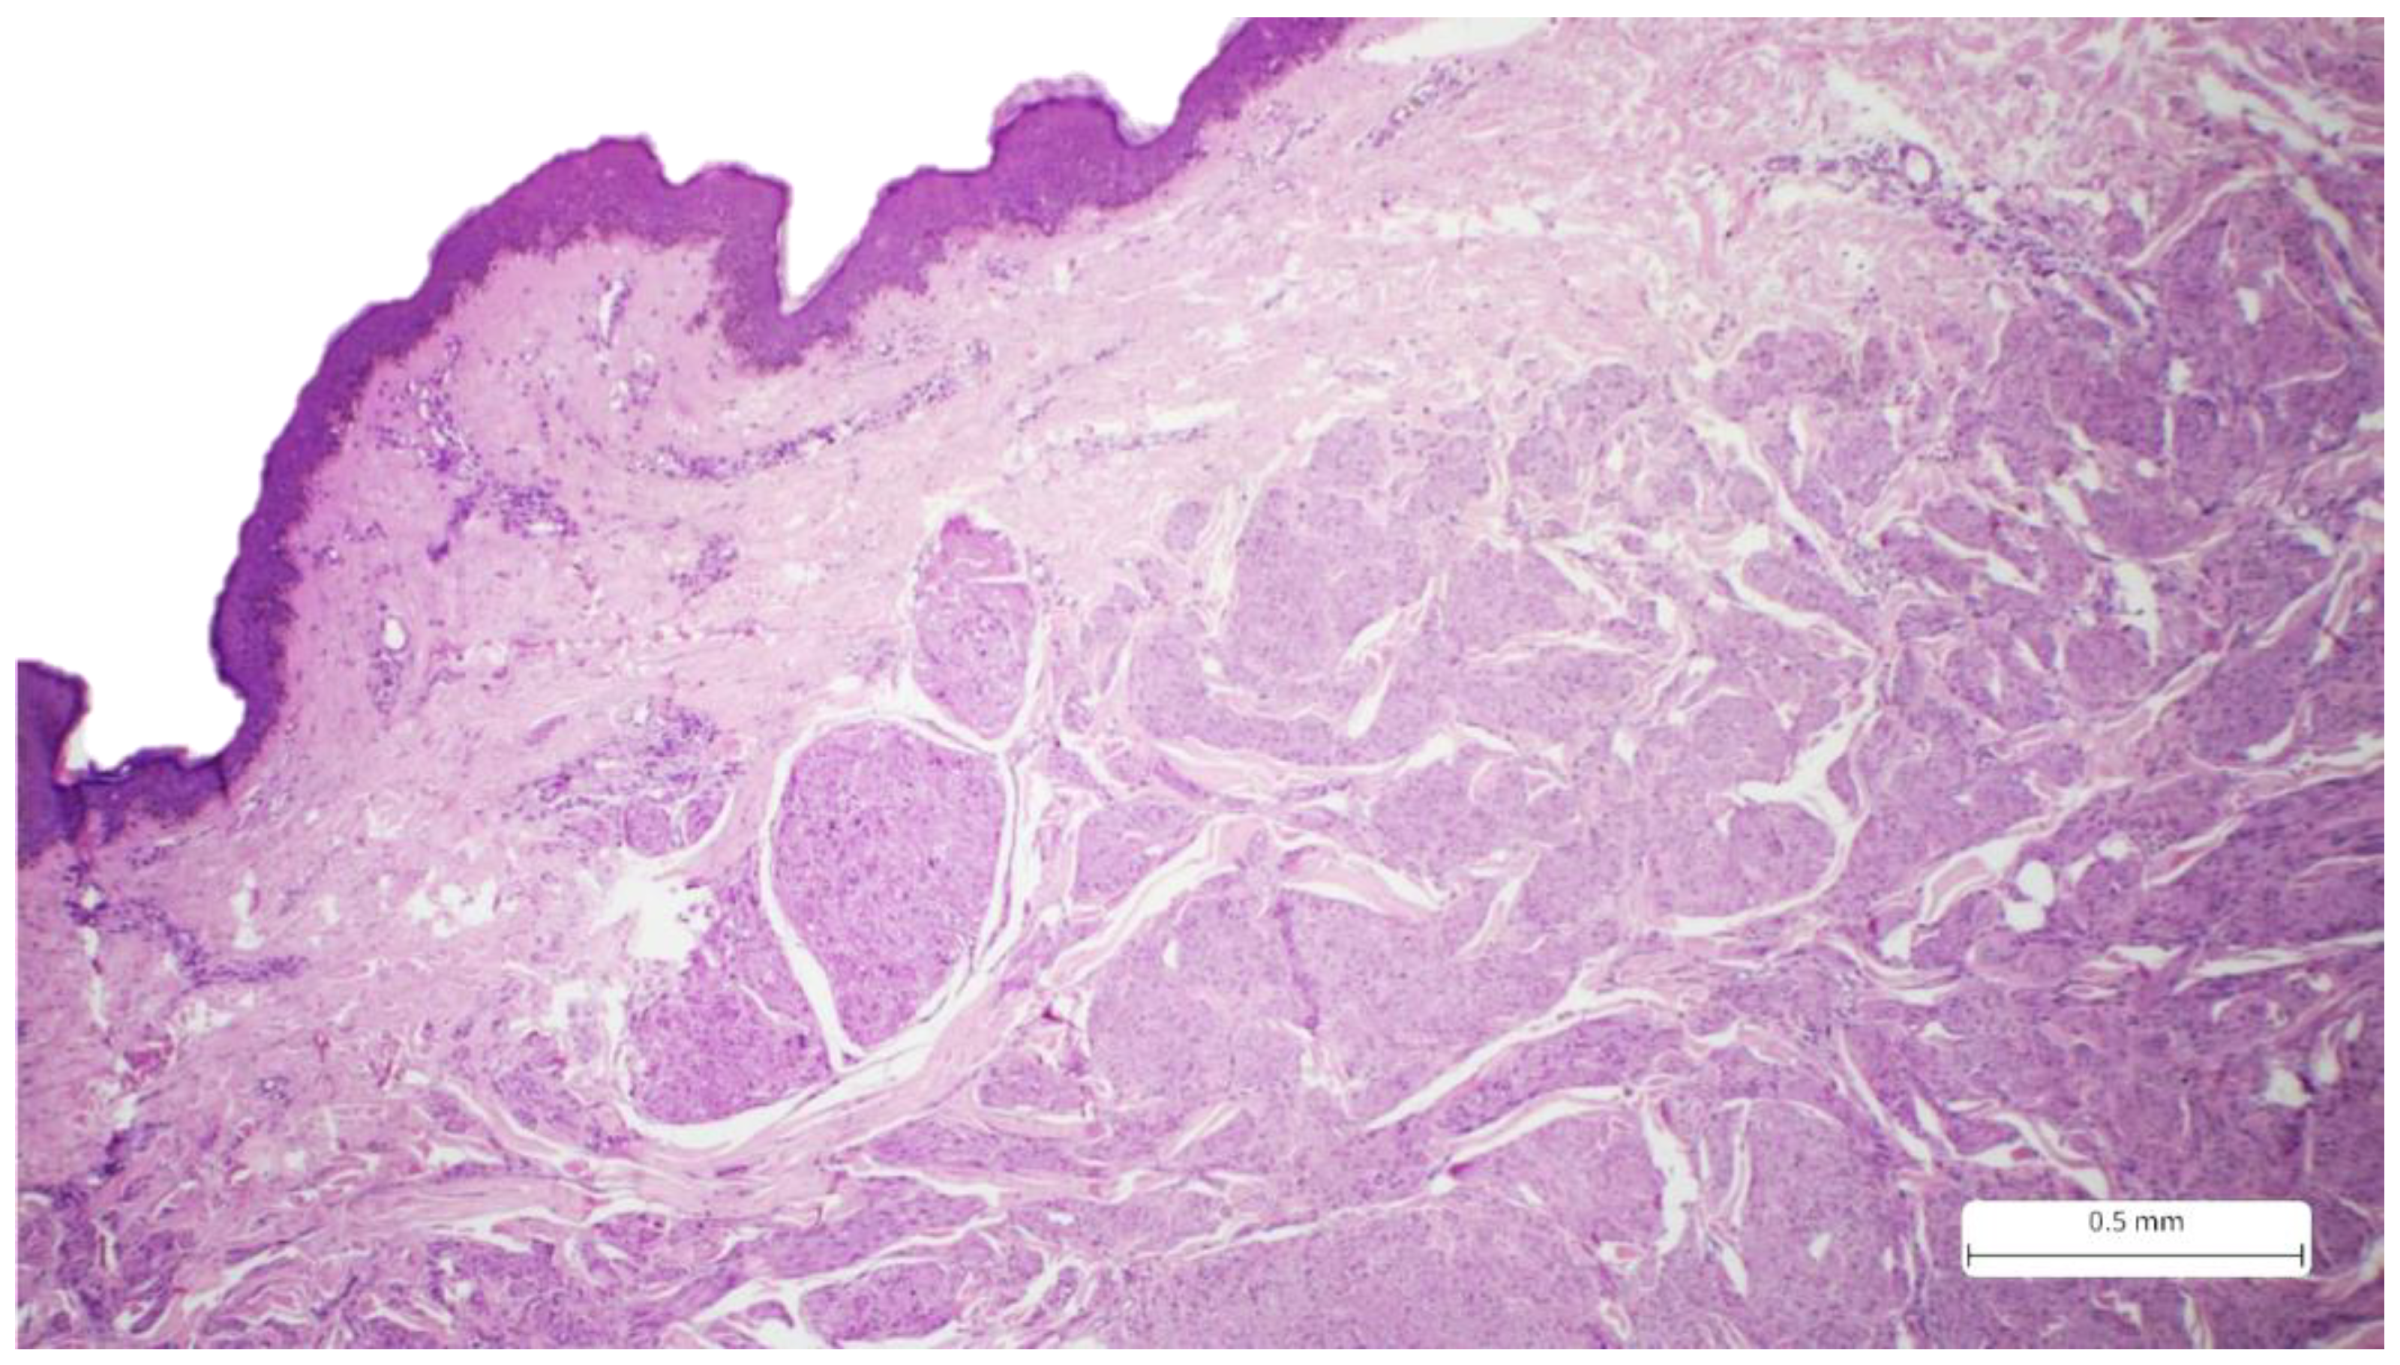

Recurrent Cutaneous Leiomyosarcoma: A Histopathological Perspective and the Quest for Complete Excision

2. Case Report